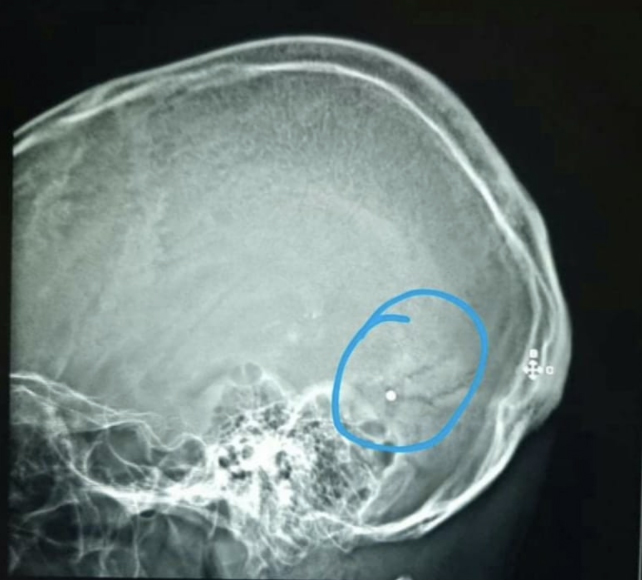

Chakhtoura said his colleague Dr Elie Saliba had been shot in the head at Saturday’s protests after working long shifts to save victims of the Beirut explosion.

Fred Bteich, a surgeon at Beirut’s Hotel Dieu Hospital, said one man was shot from a maximum distance of 15 metres (49 feet). He said one of the pellets entered the right side of the 33-year-old man’s heart, missing a major artery by 1cm (0.4 inches).

Due to the sensitive location of the pellet, surgeons were unable to remove it from the man’s heart. This has the potential to cause complications in the future, Bteich said.